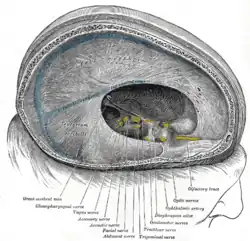

Left parietal bone. Inner surface. Dura mater and its processes exposed by removing part of the right half of the skull, and the brain

Dura mater and its processes exposed by removing part of the right half of the skull, and the brain The sinuses at the base of the skull